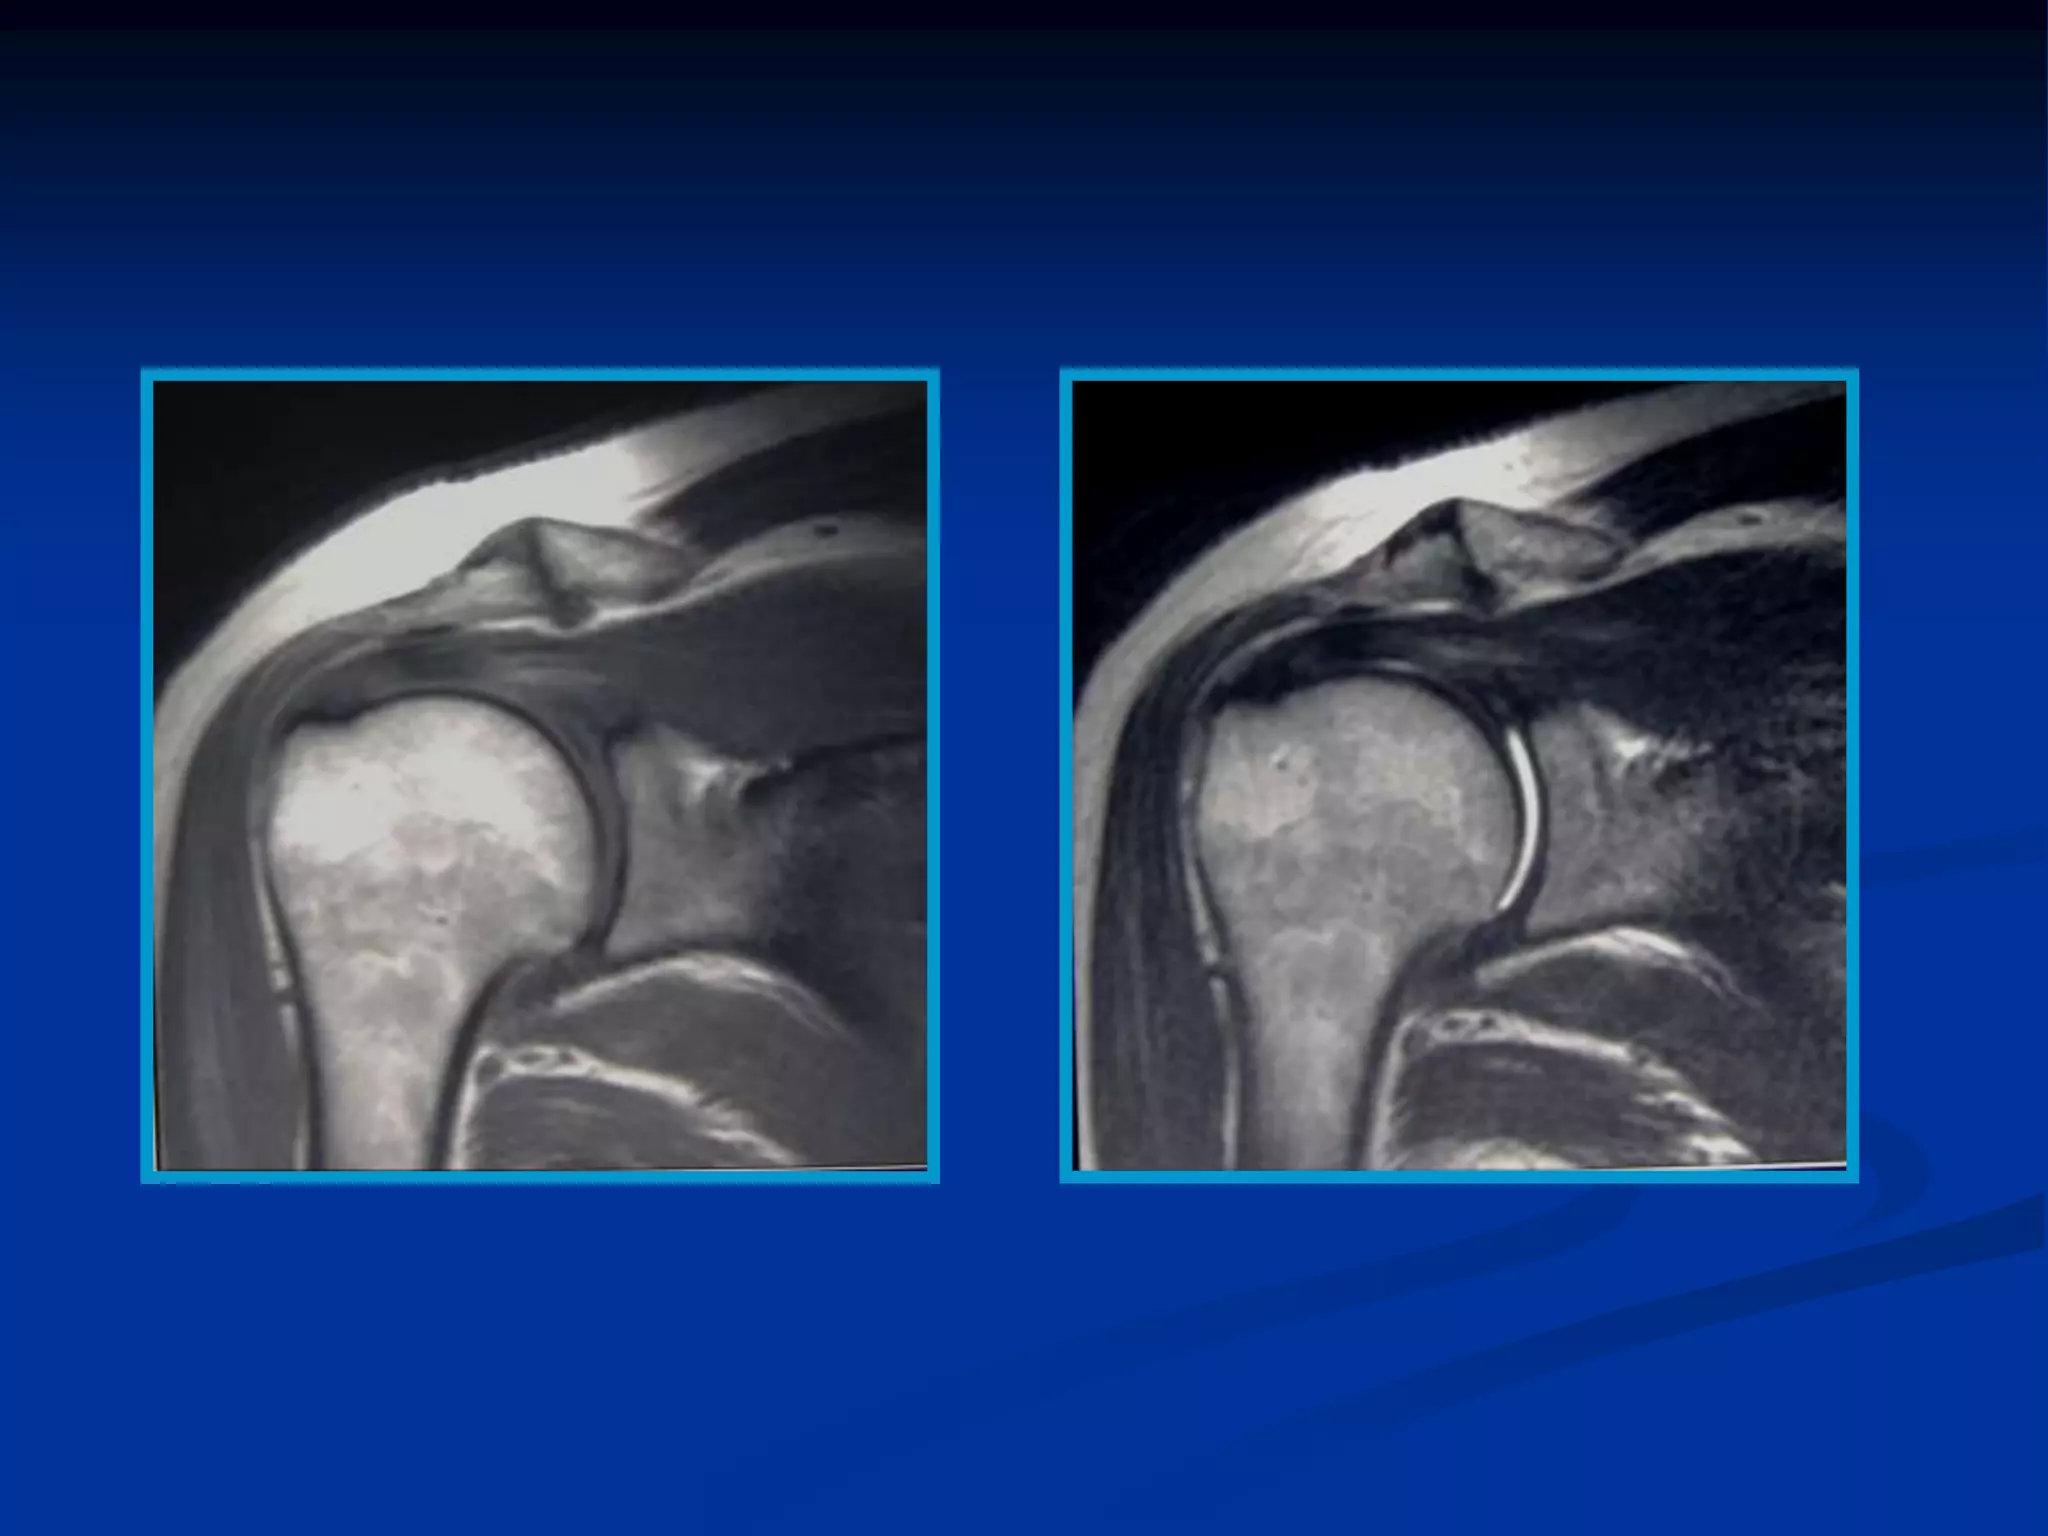

   La comparación de las imágenes en ambas

secuencias T2 y T1 es lo que proporciona la

información de la lesión.

La comparación de las imágenes en ambas secuencias T2 y T1 es lo que proporciona la información de la lesión.  La densidad protónica es una secuencia intermedia que fundamentalmente lo que detecta es la calidad de los protones.